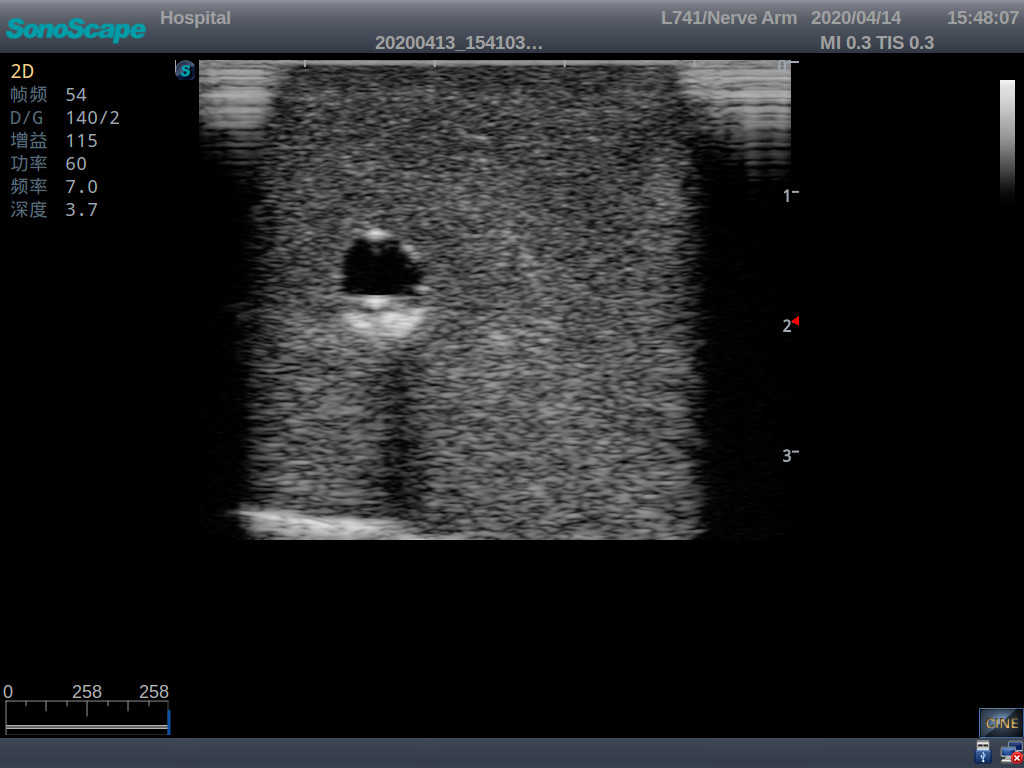

PICC Ultrasound Training Model

Model TYE1510.1

It is a model covering up from lobulus auriculae plane to the umbilical plane, and it has anatomical structures like clavicle, rib, sternocleidomastoid, jugular vein and basilic vein.

1)   Made of high molecular polymer ultrasound material, close to the real skin

2)   It can be used by real ultrasound machines

3)   Clear and real images of the tissues and organs (basilic vein and superior vena cava)